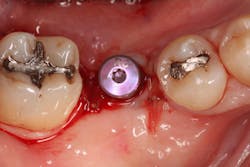

Excellent interseptal bone width was present, both buccal and lingual plates were present, and an adequate amount of bone was present coronal to the inferior alveolar nerve to allow for immediate implant placement. A sulcular incision was made around K and the adjacent teeth, and a full-thickness buccal and lingual flap was reflected. The tooth was sectioned in half, and the mesial and distal roots were elevated. The socket was degranulated with a round diamond bur and copiously irrigated with chlorhexidine gluconate 0.12% rinse. An osteotomy was completed in the interseptal area, and a bone-level 4.8- x 10-mm implant was placed to 35 Ncm. A mixture of cancellous and cortical allograft was infused with autogenous plasma-rich growth factor (PRGF), which was isolated during a preprocedural blood draw. The mixture was packed into the residual socket, slightly coronal to the implant platform to account for predictable resorption during healing. (13)

A 15- x 20-mm Ossix Plus membrane was hydrated in sterile saline for three minutes and trimmed to extend roughly 3 mm beyond the buccal and lingual extent of the bone graft and roughly 1 mm from the adjacent teeth. A sterile template is included in each membrane package; it can be trimmed to the appropriate dimensions and superimposed on the Ossix Plus membrane for final trimming to ensure the exact dimensions desired are obtained. This membrane can also be sutured, if necessary. When this technique is used, it is important to pass the suture needle through the membrane at a 90-degree angle to avoid tearing the membrane.

At this point, releasing incisions (vertical incisions and/or periosteal releasing incisions) can be made to achieve primary closure or to leave the membrane exposed and let the area heal by secondary intention. With the Ossix Plus membrane’s increased resistance to bacterial collagenase and the stresses of the oral environment, I feel comfortable leaving the membrane exposed and allowing the attached gingiva to heal over the membrane. This will result in reduced swelling and discomfort during healing, and there is less risk of damaging the mental nerve as it exits the mental foramen and fans laterally into the tissue. Attached gingiva around an implant will facilitate a more accurate impression, easier delivery of the restoration (and increased resistance to cement penetrating subgingivally), and easier hygiene for the patient. Also, when the implant is uncovered after healing, a tissue punch can be used, and there will generally be no need for a flap and sutures, thus improving the patient experience. Conversely, primary closure is imperative when performing a lateral or vertical ridge augmentation with or without simultaneous implant placement. Generally, when the extraction socket walls are intact, leaving the membrane exposed and allowing attached gingiva to grow over the membrane is predictable.

In this case, I placed an autogenous fibrin clot, which was isolated from the fractionated blood draw, over the Ossix Plus membrane and sutured, without obtaining primary closure, using a CV-5 Gore-Tex (W.L. Gore & Associates Inc.). This technique is designed to help facilitate the formation of a blood clot over the Ossix Plus membrane. It can be used with the addition of a collagen plug over the membrane, or you can just suture and allow a natural clot to form.